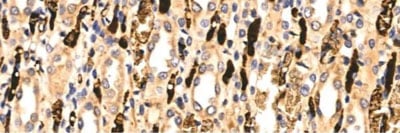

IHC (Immunohistochemisry)

(AAA320806 at 1/100 staining Rat kidney tissue by IHC-P. The sample was formaldehyde fixed and a heat mediated antigen retrieval step in citrate buffer was performed. The sample was then blocked and incubated with the primary antibody at 4°C overnight. An HRP conjugated anti-Rabbit antibody was used as the secondary antibody.)